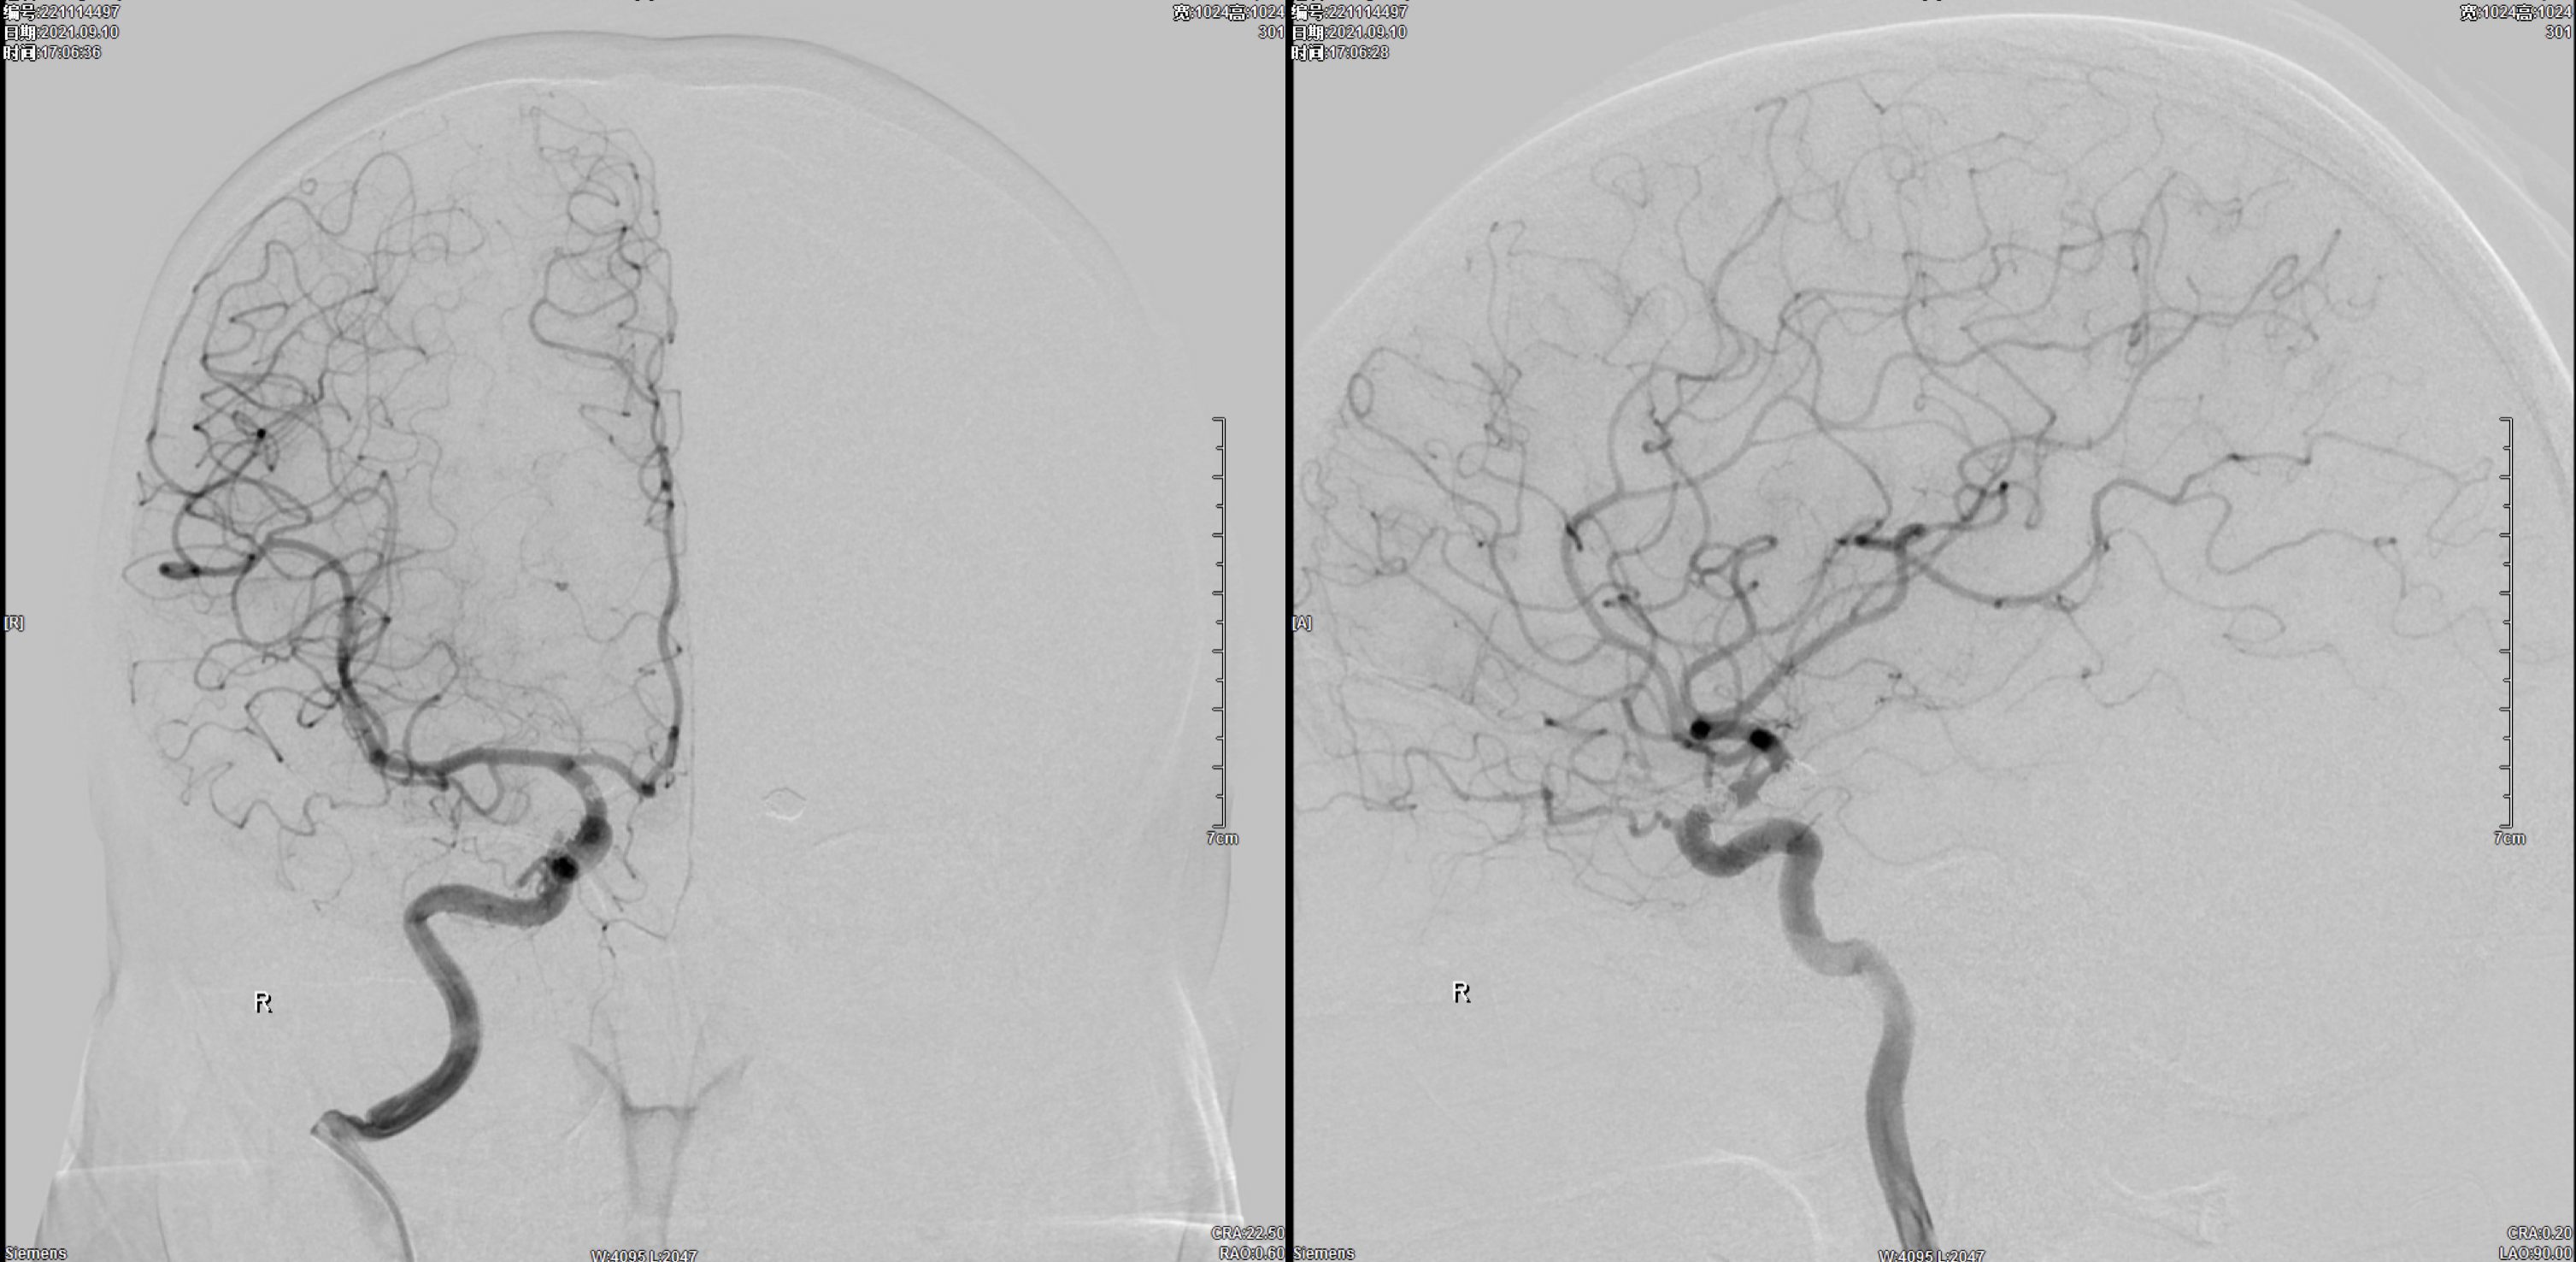

术后3月复查右侧颈内动脉正侧位造影:动脉瘤栓塞满意,未见残留及复发。

术后3月复查左侧颈内动脉正侧位造影:动脉瘤栓塞满意,未见残留及复发。